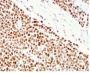

Positive Control

HCT116 or HeLa cell lysate (WB). Human colon carcinoma (IHC).

Antibody target cellular localization

Nucleus

Flow, intracellular (verified), IF (verified), IHC, FFPE (verified), WB (verified)